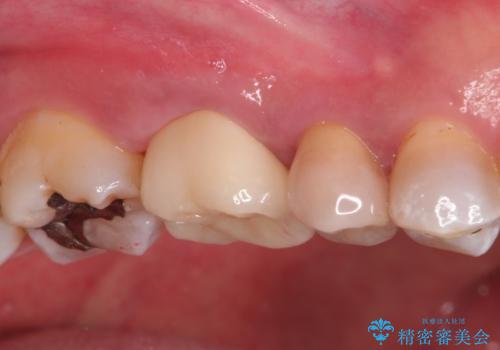

- 定期検診にて、奥歯の頬側歯肉にサイナストラクトが発見された患者様です。

根管治療から歯冠修復まで行っております。

サイナストラクト(瘻孔)から原因歯を特定し治療を行っております。根管治療を行った歯牙は破折リスクが高くなるため被せものによる治療を提案しております。